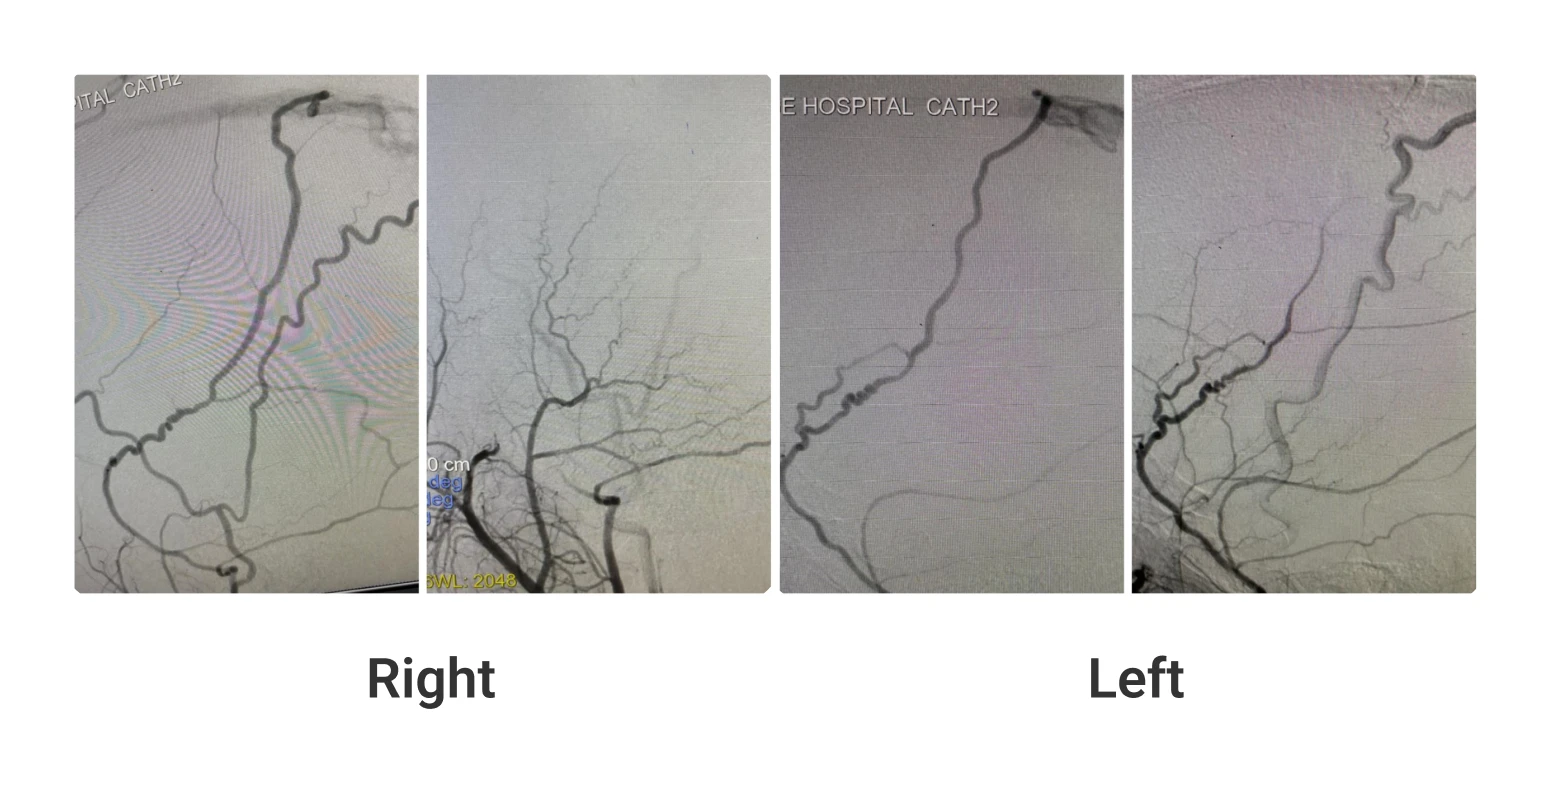

THE FIRST EVER NEUROINTERVENTION CASE AT THE TERTIARY CARE KALAINGAR CENTENARY SUPER SPECIALITY GOVERNMENT HOSPITAL, CHENNAI, TAMIL NADU, INDIA. 30 […]